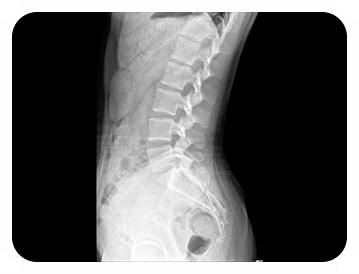

그래서 엑스레이를 통해 뼈 간격을 확인하고, 필요에 따라

CT 등을 활용해 신경 압박이나 염증 상태를 살펴봅니다.